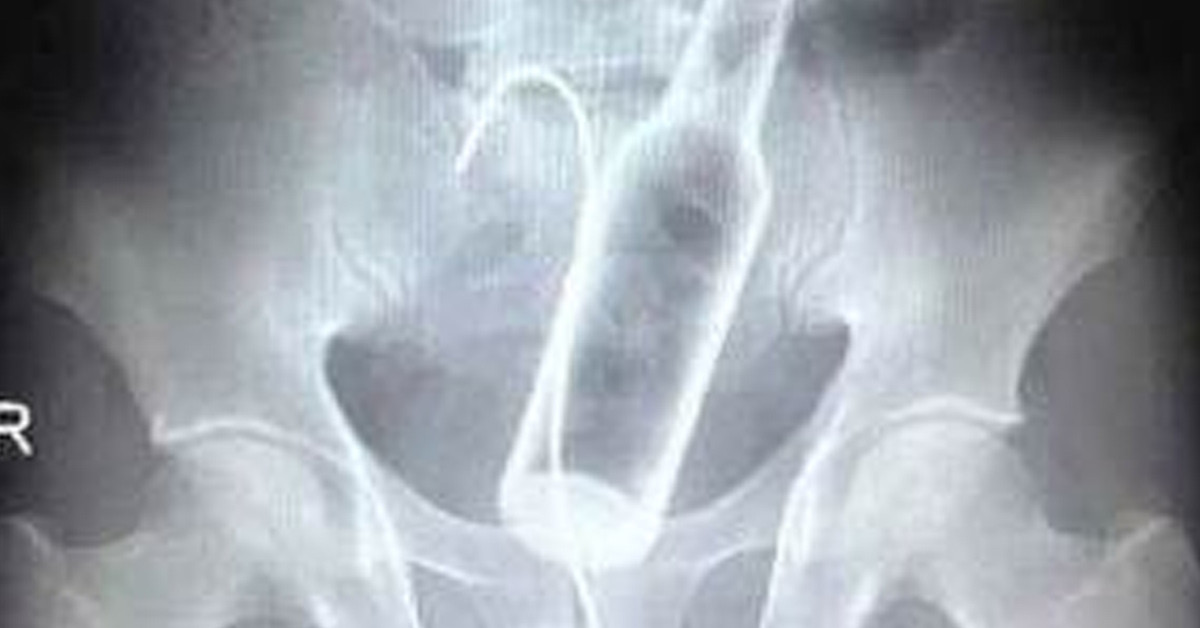

Şanlıurfa'da basur problemi sebebiyle hacamat yaptıran adam, bir hafta geçtikten sonra anüs bölgesinde rahatsızlık hissetti. Çekilen röntgen filminde anüs bölgesinde çay bardağı görüldü. Bardak ameliyatla çıkarıldı.